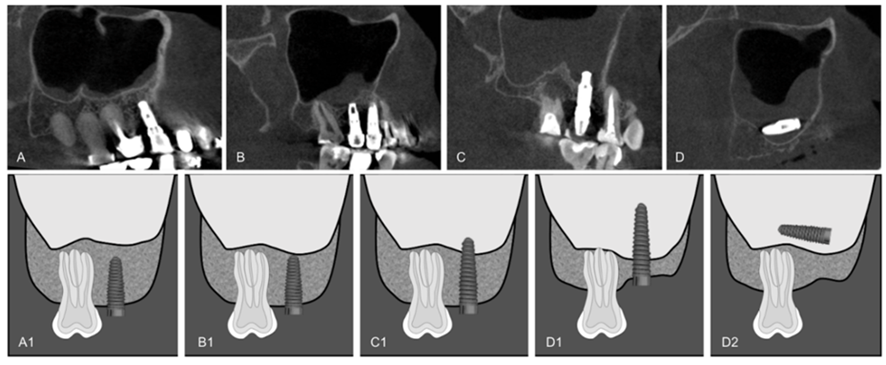

Odontogenic sinusitis most commonly develops as a result of infections originating from the upper jaw (maxilla) posterior teeth spreading to the maxillary sinus. The roots of the upper posterior molar teeth are very close to the sinus floor in most people. In some individuals, the tooth root can extend directly into the sinus. Therefore, tooth root infections, failed root canal treatments, periapical abscesses, oroantral fistulas formed after tooth extraction, sinus lifting procedures, and dental implants can lead to maxillary sinusitis.

Yes, an increase in odontogenic sinusitis rates has been reported in the literature over the last 10-15 years. The most important reasons for this are: the increase in implant applications, the widespread use of sinus lifting surgeries, and the rise in implant demands at advanced ages. However, an important point needs to be emphasized here: Properly planned implants performed with appropriate technique do not cause sinusitis.

- Implant placement too close to the sinus floor

- Perforation of the sinus membrane

- Peri-implantitis developing after implant placement